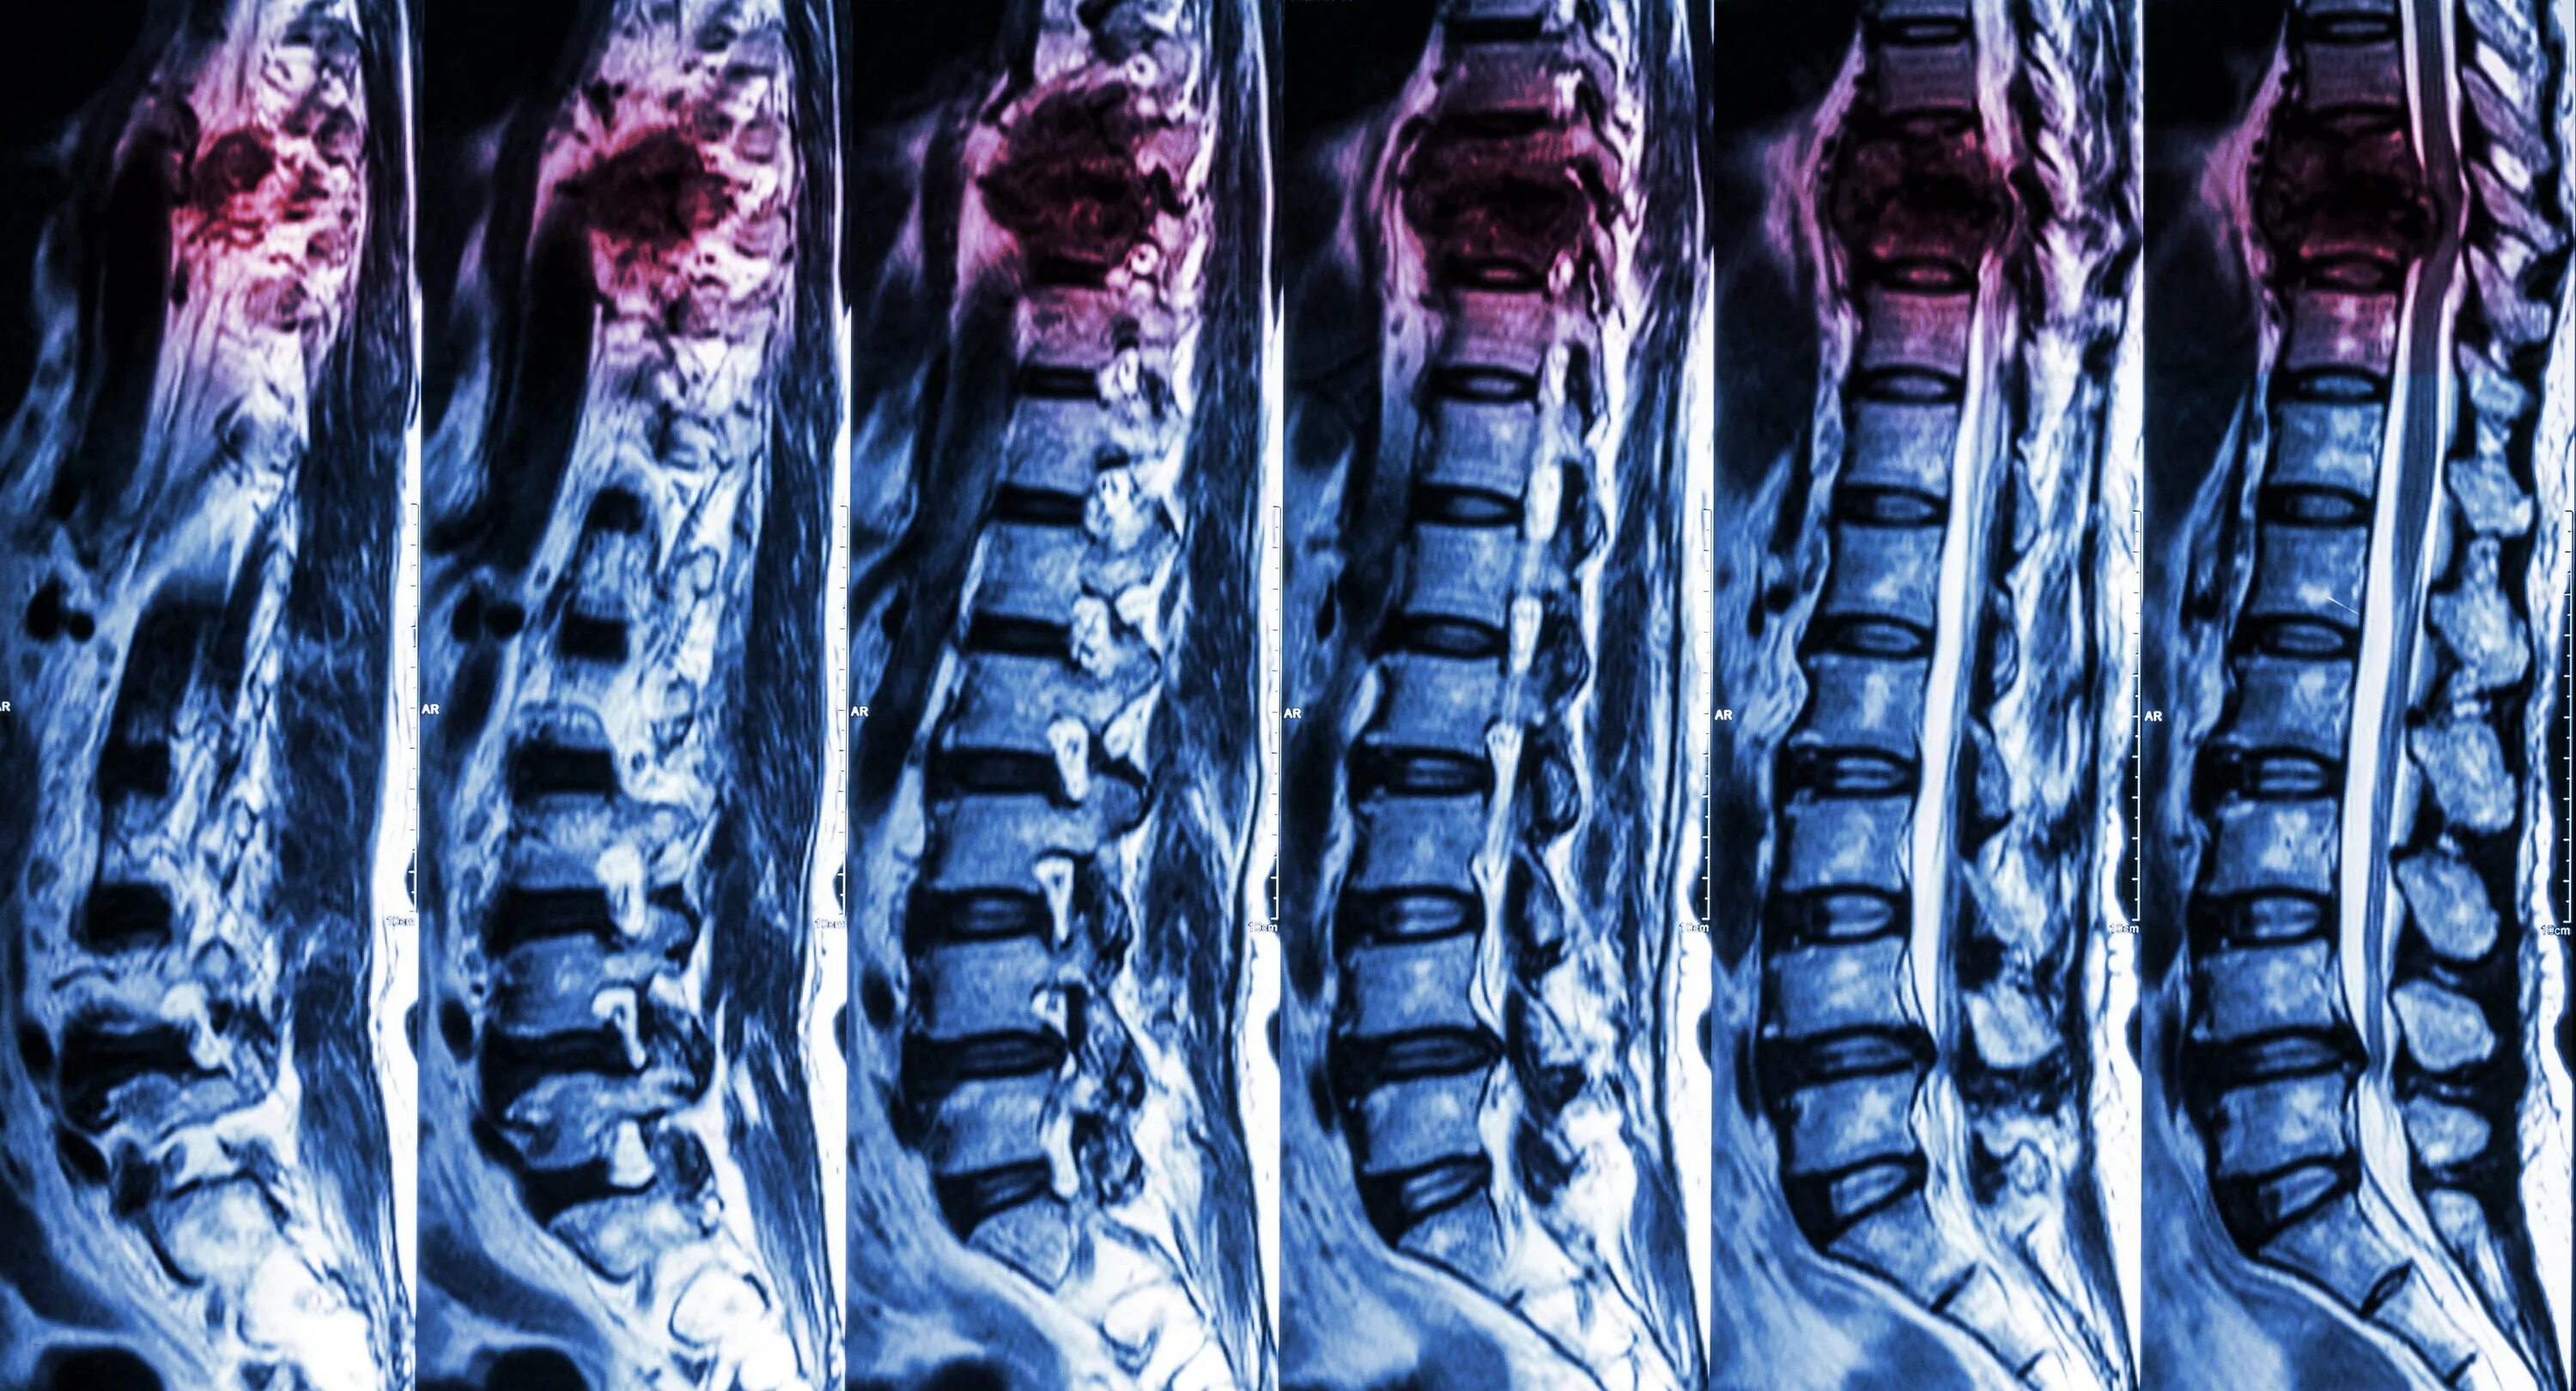

Чем отличается кт от мрт поясничного отдела